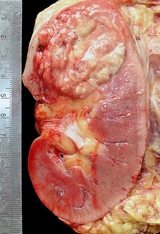

Prof. Dr. Lara: Böbrek kanseri tedavisinde son 10 yıl içerisinde bir paradigma değişikliği söz konusudur. Tedavide çoğunlukla sitokinler kullanılırken, moleküler olarak hedeflenmiş tedavilere yönlenildi. Bu da, hastalık sonucunu iyileştirdi. Bu tedaviler sayesinde tümörler küçüldü, progresyonsuz sağkalım süresi ve daha da önemlisi genel sağkalım süresi uzadı. Kısacası, sitokin tedavisi ile elde edilen sonuçlar, daha yeni ve etkili etken maddeler ile elde edilmeye başlandı.

Böbrek kanseri, diğer kanserlerden biraz daha farklı; çünkü bütün hedeflenmiş ilaçlar, yararlanacak hasta alt grubu belirlenmeden önce geliştirildi. Bu konuda yapılan biyolojik çalışmalar devam ediyor. Hasta popülasyonunu genişleterek klinik çalışmalar yapabilir ve belki bazı biyobelirteçler de bulunabilir.

Prof. Dr. Lara: Erken evre böbrek kanseri hastaları için, yani birinci basamak tedavi cerrahi rezeksiyon olan Evre I, II ve III hastalar için, nefrektomi sonrası verilen standart bir tedavi yok. Bu nedenle, biz nefrektomi yapılan ve cerrahi sonrasında hastalığın bulgusuna rastlanmayan erken evre böbrek kanseri hastalarına klinik çalışmalara katılmalarını öneriyoruz. Amerika’daki grubum (Güneybatı Onkoloji Grubu-SWOG), şu anda geniş ölçekli, faz III çalışma yapıyor ve tamamen rezeke edilen böbrek kanseri hastalarında plaseboya kıyasla mTOR inhibitörü everolimusu karşılaştırıyor.